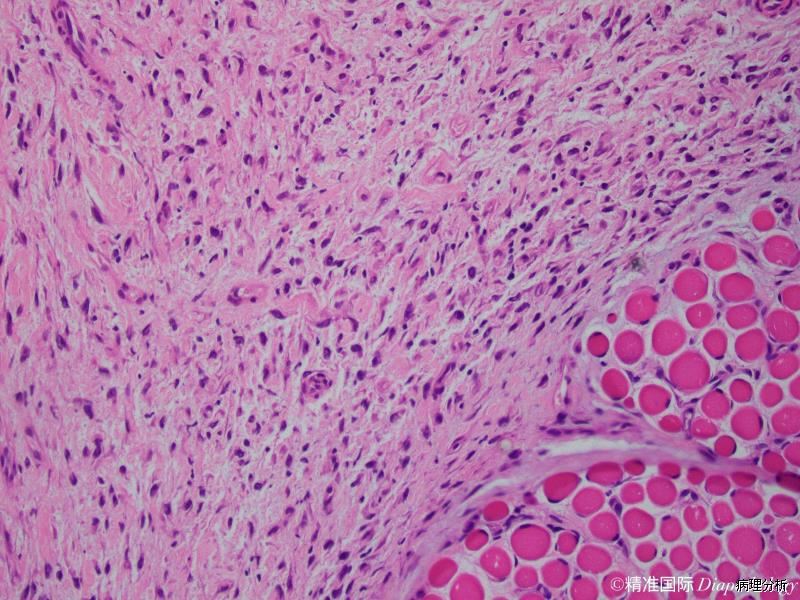

由大量增生的纤维母细胞、肌纤维母细胞、节细胞样细胞和形态上介于两者之间的过渡形细胞组成;

纤维母细胞、肌纤维母细胞呈梭形或胖梭形,也可呈蝌蚪状和不规则形,核膜厚,染色质呈空泡状,可见核仁,核分裂像多少不等,但无病理性核分裂;

间质含有多少不等的黏液样物质和胶原纤维;

病变穿插于横纹肌纤维之间,在横切面上常形成“棋盘”样,不累及横纹肌纤维本身;